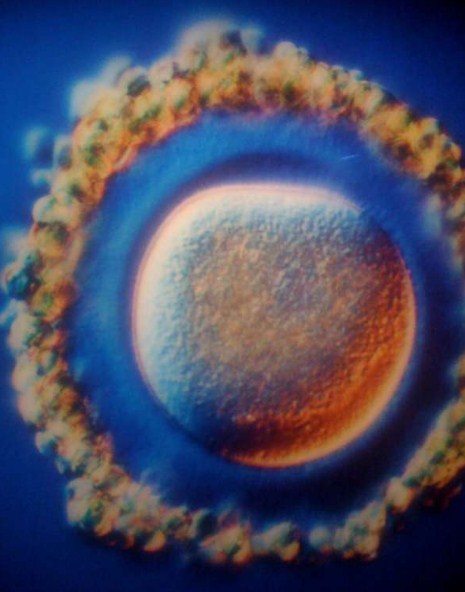

Фотографът Ленарт Нилсън е прекарал 10 години в документиране на човешкия ембрион, от зачеването до раждането.

Светът за първи път научава за Ленарт през 1965г, когато списание LIFE публикува 16 страници с негови снимки на човешки ембриони. Снимките веднага са преиздадени в други популярни издания. Микроскопите и фотоапаратите са страст на Ленарт от дете. С времето амбицията му дава на света възможност да види красотата на човешкото тяло на микро ниво. Той успява да направи първите си снимки на зародиш още през 1957г, но тогава те все още не са достатъчно добри.

Нилсън е успял да направи най-прецизните си кадри с помощта на цитоксоп – медицински инструмент, с който се изследва вътрешността на пикочния мехур. Той е закачил камера с малка лампа на върха й, след което е направил хиляди снимки на живота на ембриона в утробата на майката.

За първи път хората могат да видят със собствените си очи зачеването и най-ранните стадии на човешкото развитие.

Сперматозоидът отблизо. Главичката му съдържа целия генетичен материал.